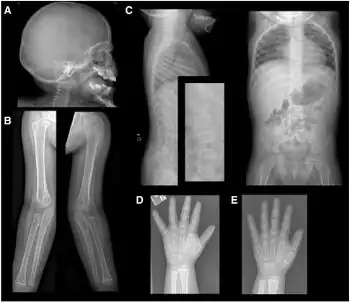

Infants with LPI are usually symptom-free when breastfed because of the low protein concentration in human milk, but develop vomiting and diarrhea after weaning. The patients show failure to thrive, poor appetite, growth retardation, enlarged liver and spleen, prominent osteoporosis and osteopenia,[2] delayed bone age and spontaneous protein aversion. Forced feeding of protein may lead to convulsions and coma. Mental development is normal if prolonged episode of hyperammonemia can be avoided. Some patients develop severe pulmonary and kidney complications. High levels of plasma glutamine and glycine are observed.